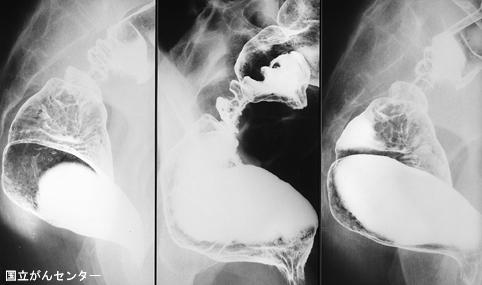

症例提示(所在地,施設名等): 東京都・ 国立がんセンター中央病院と九州がんセンターの共同作成

疾患(病理主体)の分類腫瘍様病変/子宮内膜症

部位(臓器別)大腸/直腸

検査方法X-P

病変の最大径(ミリ)40以上